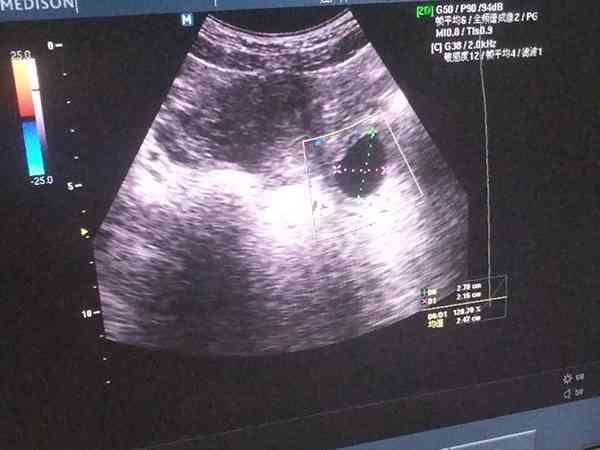

这种情况如果希望继续观察,顶多再过一周复查超声,如果仍不能看到胎心,可以确认是胎停育,建议及早清宫。一般情况下停经8周应该能看到胎芽胎心了,仍然没有胎心,要考虑胎停育可能。

1. 1. 平均孕囊直径≥25mm时未见胎芽;

2. 2. 头臀径≥7mm时未见胎心搏动;

3. 3. 无卵黄囊的孕囊,在2周后仍然未见胚芽、胎心;

4. 4. 有卵黄囊的孕囊,在11天或更长时间后未见胚胎及胎心搏动;

5. 5. 孕6周及以上,仍无孕囊,或虽有孕囊但变形枯萎。

因为现在已经孕8周了,孕囊直径也有28mm,并且还没见胎心胎芽,符合上面的第1条,因此考虑胎停育的诊断。